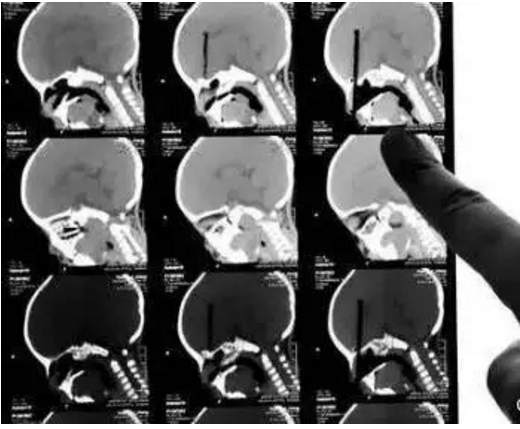

筷子插入小朋友眼球的CT三维重建片